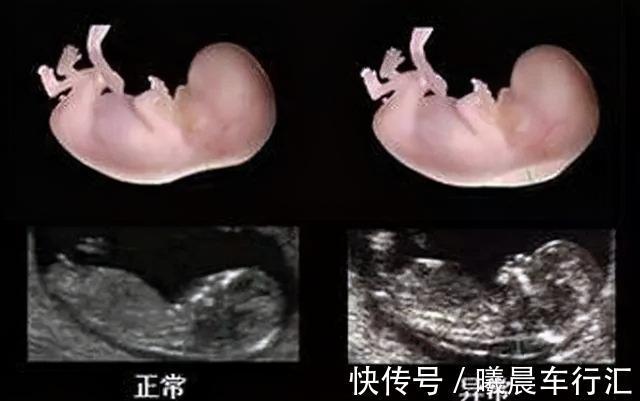

预防“唐氏综合征”,这两项检查很关键?第一项检查:NT检查指的是检查胎儿的“颈项透明层”,看胎儿颈椎的厚度,并参考临床标准,来确定胎儿存在唐氏综合征的风险。因此,这项检查又被称为“早唐筛查”。【检查时间】:怀孕11-14周是最好的检查时间,一般在孕12周产检时一起做。【检查方式】:B超检查,不需要憋尿。